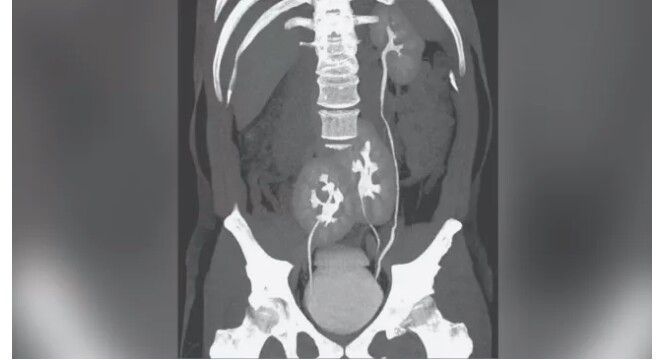

A man in Brazil surprised his doctors when a scan showed he had not two, but three kidneys — a very rare condition. The 38-year-old man initially sought medical care for severe back pain, according to a report of the case, published May 6 in The New England Journal of Medicine. A CT scan showed that his back pain was due to a herniated or "slipped" disk, a relatively common condition in which part of a cushion-like disk between the spinal vertebrae moves out of place. But his doctors couldn't help but notice that the man had an unusual anatomical feature. Instead of the usual two kidneys seen in a typical person, the man had three: a normal-looking kidney on his left side and two fused kidneys located near the pelvis, the report said. Having three kidneys is rare, with fewer than 100 cases reported in the medical literature. The condition is thought to arise during embryonic development, when a structure that typically forms a single kidney splits in two. The man didn't need any medical attention for his extra kidney, but he did receive oral painkillers for his back pain, the report said.